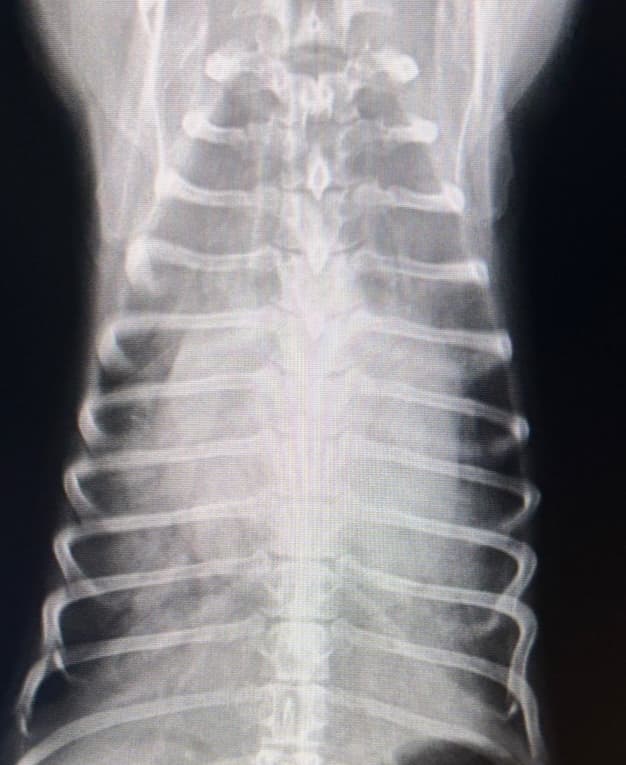

変形性脊椎症(2024/02/06)

脊椎に骨増殖と呼ばれる変形が起きる疾患で、加齢に伴い発症率は上昇します。多くは無症状ですが、一部は慢性的な痛みを生じて日常生活に支障を来たすこともあります。持続的な脊椎への負担や椎間板の変性などが原因と考えられており、痛みがある際には消炎鎮痛剤の内服や運動制限、温熱療法などの治療が推奨されます。動きが鈍い、歩きづらそうなどの症状がある場合にはお早めにご相談下さい。